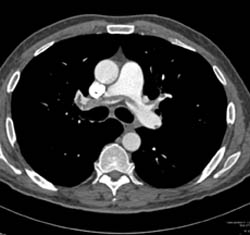

Diagnosis

Pe